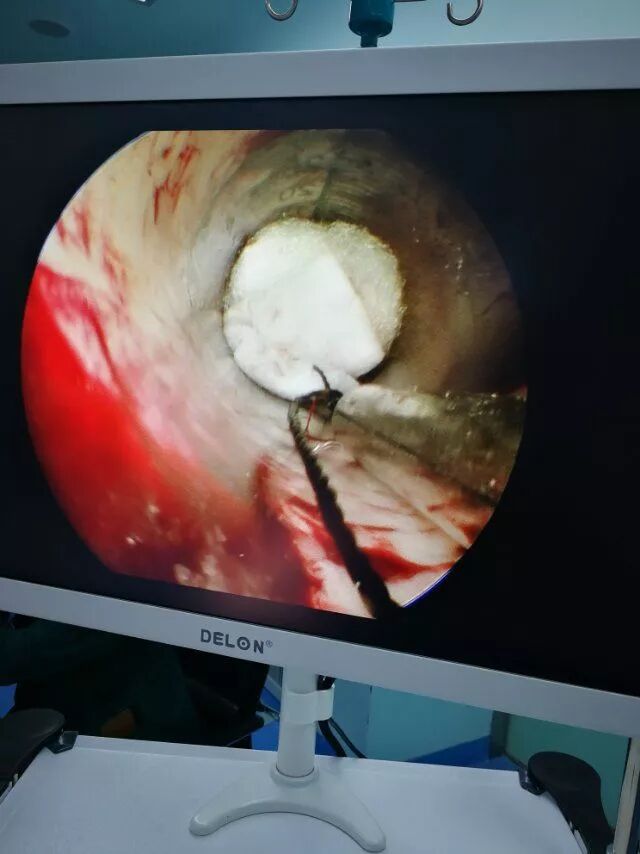

内镜下清血